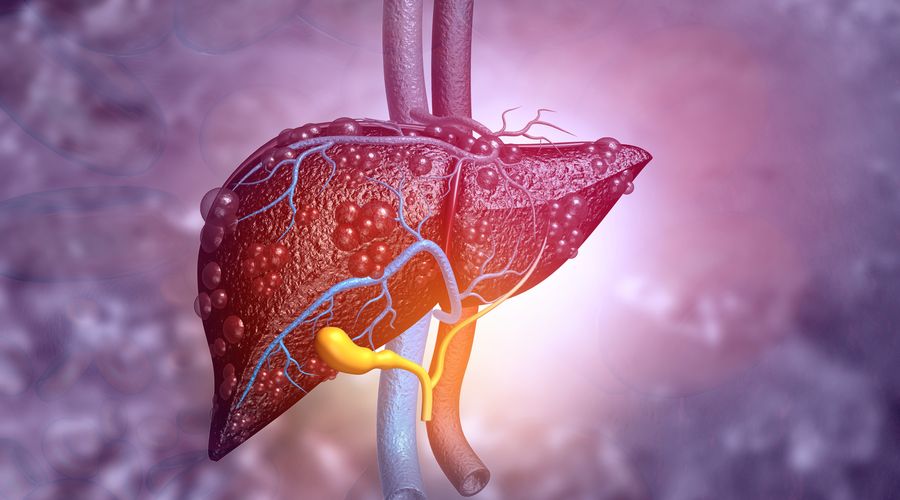

Yapay tatlandırıcılı ve şekerli içecekler, karaciğer yağlanması riskini artırıyor

MASLD, günümüzde dünyanın en yaygın kronik karaciğer hastalığı olarak kabul ediliyor ve dünya nüfusunun %30’undan fazlasını etkiliyor. Hastalık, sinsi bir şekilde ilerleyerek iltihaplanma, siroz ve karaciğer kanseri gibi ciddi sonuçlara yol açabiliyor.